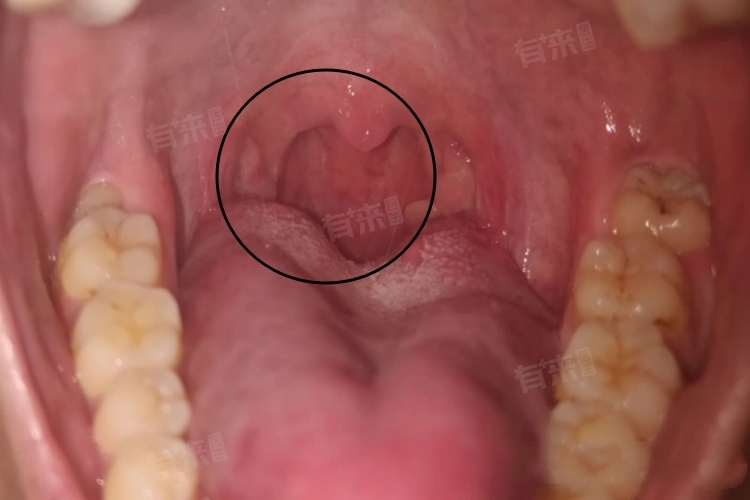

扁桃体白膜脱落的时间通常在术后5-10天,但具体时长受多种因素影响。扁桃体手术会造成局部组织损伤,术后创口表面会形成一层白膜,这层白膜对创口起到保护作用,可防止感染、减少出血。

白膜脱落是一个渐进的过程。初期,白膜边缘开始松动,患者可能感觉咽部有异物感或轻微刺痛。随着脱落进展,松动的白膜部分会逐渐与创口分离,在此期间,若患者用力咳嗽、吞咽过硬食物,可能导致白膜提前大面积脱落,增加出血风险。当白膜完全脱落后,创口表面会露出新鲜的肉芽组织,此时仍需注意护理,避免感染,直至创口完全愈合。整个脱落过程中,患者应密切关注自身症状变化,如有异常及时就医。